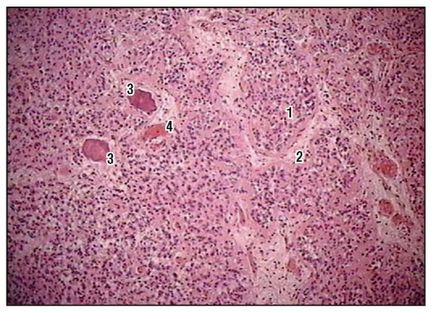

Fig. 162. Epifiză. Lobule (colorare cu hematoxilină și eozină, creștere mică): 1 - lobule; 2 - septul interlobular de țesut conjunctiv; 3 - concreții epifize; 4 - vasele de sânge